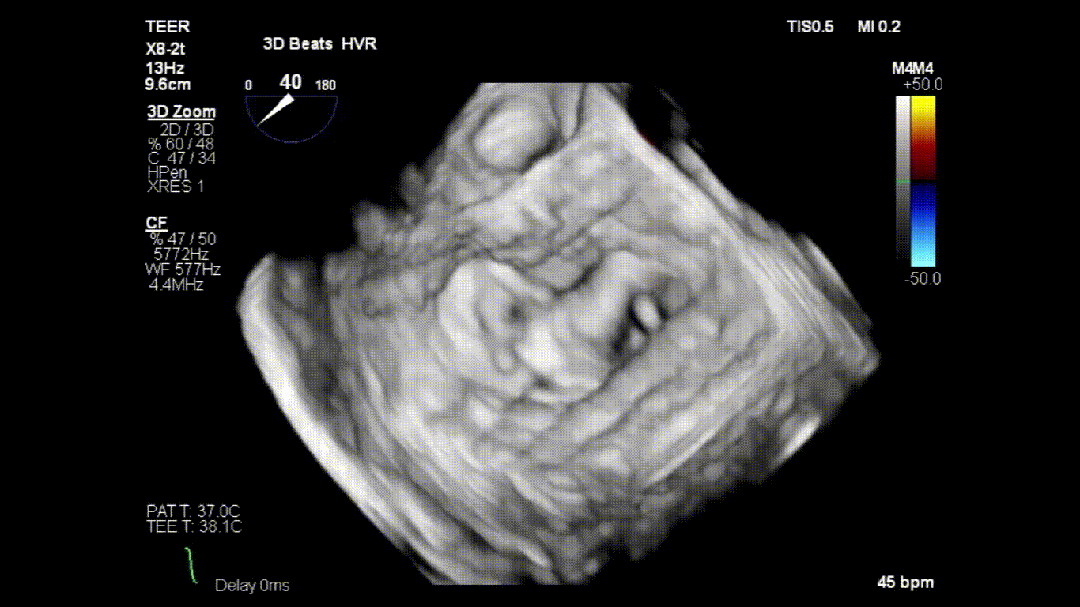

本次培训的“重头戏”—— 两台高难度 TEER 手术沉浸式观摩,将培训氛围推向高潮。手术病例分别为 “P2 宽大脱垂病变” 与 “早期 Barlow 病变”,由厦门大学心血管病医院团队与浙江大学附属邵逸夫医院团队协同完成。术中,专家团队操作精准、配合默契,不仅完美展现了 TEER 技术在复杂病例中的应用优势,更通过实时讲解,让学员直观掌握手术关键步骤、解剖评估要点与应急处理思路。

病例1:

病例2: